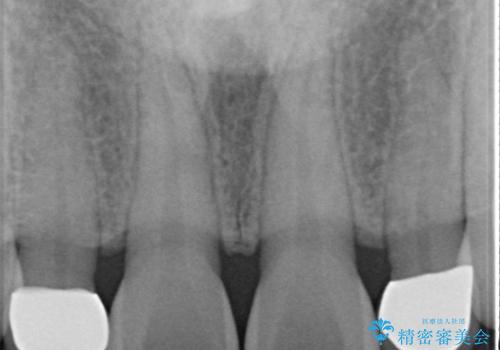

- 歯の形が気になるということで以前入っていたプラスチックのものから、セラミックでの治療を希望されたので行いました。

色や形をこだわりたいということで、当院最上位ランクのエクセレントにて治療を行いました。

以前使用していた被せ物を除去して、仮歯に置き換えます。

その後、歯の最終的な形を作って型取りを行います。

当院で患者様の口腔内の写真を撮影し技工士さんに指示を出して完成します。

患者様はかなり喜ばれておりました。